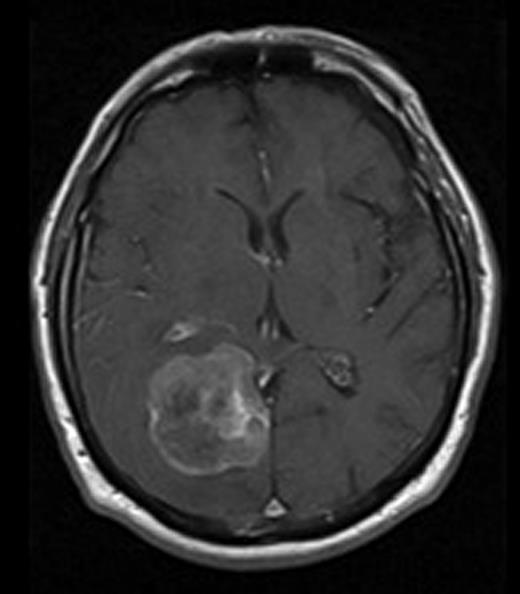

Eighteen months after his initial presentation, he experienced progressive left-sided weakness and left-sided homonymous hemianopia. An MRI scan of his brain showed extra-axial right occipitoparietal enhancing mass (43 × 43 × 47 mm) with surrounding vasogenic oedema. It was isointense to grey matter on T2 and abutting the falx cerebri with midline shift and effacement of the right lateral ventricle (Fig. 2). The lesion was approached through a right occipital craniotomy and entirely removed in a piecemeal fashion. At surgery, it appeared as a greyish-white firm vascular mass with a clear cleavage plane with the surrounding brain. He recovered well after surgery. His left-sided weakness improved significantly with some improvement in the hemianopia. Histopathology revealed metastatic malignant mesothelioma (Fig. 3). The patient had good recovery and was discharged home. On 6-week follow-up, the patient continued to improve with significant improvement in his quality of life.

MRI image of brain with gadolinium contrast showing enhancing mass in the right occipital lobe.